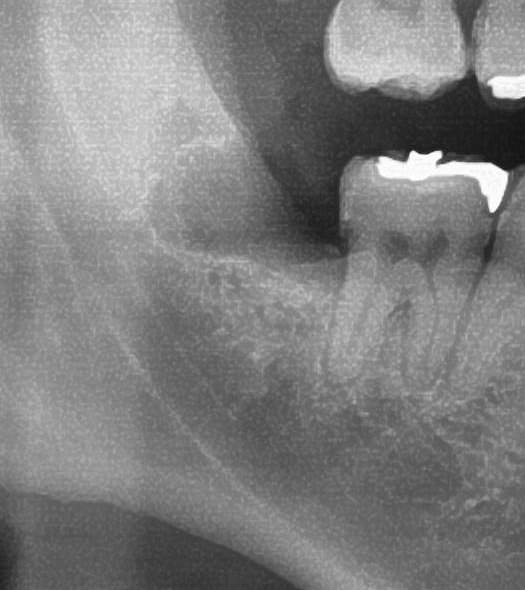

まずお口の中を見てみると、右下の親知らずは頭の一部分が少し見えている状態でした。

次にパノラマ写真を撮影してみると、右下の親知らずは手前の歯の歯を押すように斜めに生えているのが確認できました。